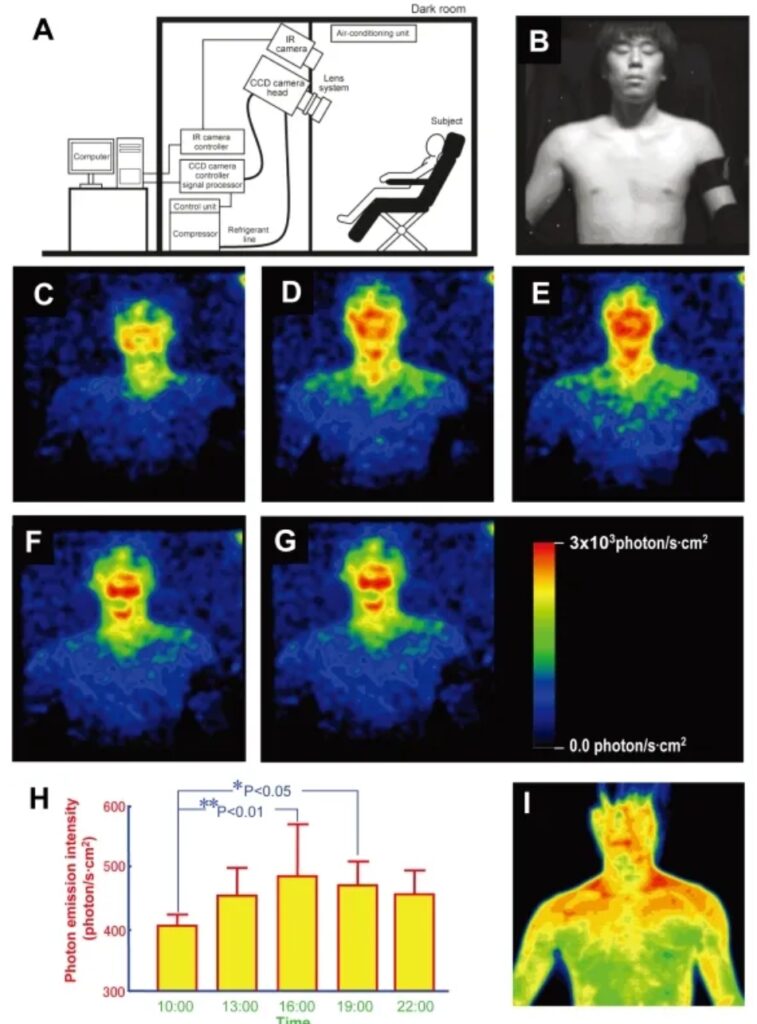

Una de las fotos de la prueba Kobayashi

Fotos de la prueba Kobayashi